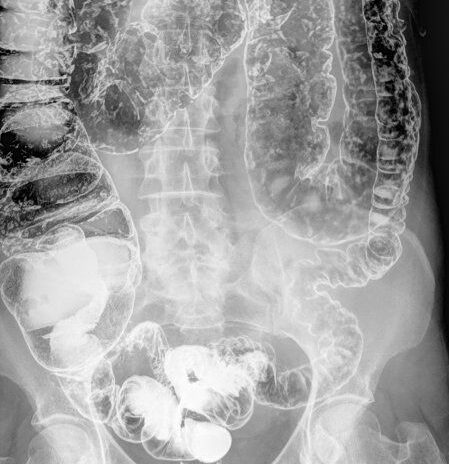

El enema opaco no debe realizarse en caso de embarazo, alergia al bario, inflamación rectal grave o si se ha realizado recientemente una biopsia rectal.El enema opaco es una técnica de diagnóstico utilizada para evaluar el intestino grueso, el colon, el recto y el ano mediante rayos X y la administración de un contraste de sulfato de bario. Este examen permite detectar posibles problemas intestinales como pólipos, diverticulitis o enfermedades inflamatorias del intestino.

Una vez que el paciente está preparado, el examen de enema opaco puede llevarse a cabo. El procedimiento se realiza sin anestesia y generalmente dura alrededor de 40 minutos. Se introduce una sonda rectal y se administra el contraste de bario. Luego se realizan varios rayos X para evaluar el intestino y obtener imágenes claras de posibles anomalías.